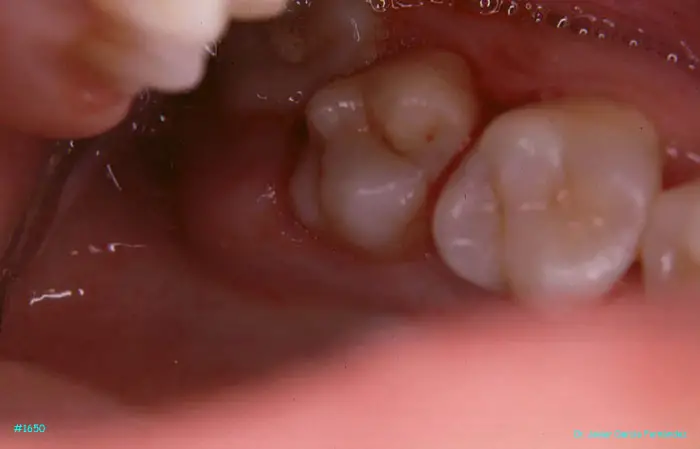

image 163